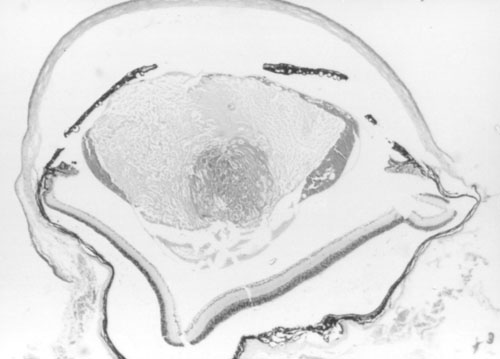

Figure 2. Histology of Ccw/+ eyes

A. Normal littermate 10 days post partum. B. Ccw/+ 10 days post partum. Some vacuolation of the lens is visible. C. Ccw/+ 20 days post partum. Lens fibers are becoming swollen and disorganized. D. Ccw/+ 4-6 weeks post partum. Lens fibers are largely degraded. E. Ccw/+ 14 weeks post partum. Only the lens capsule and some epithelium remain.

D.